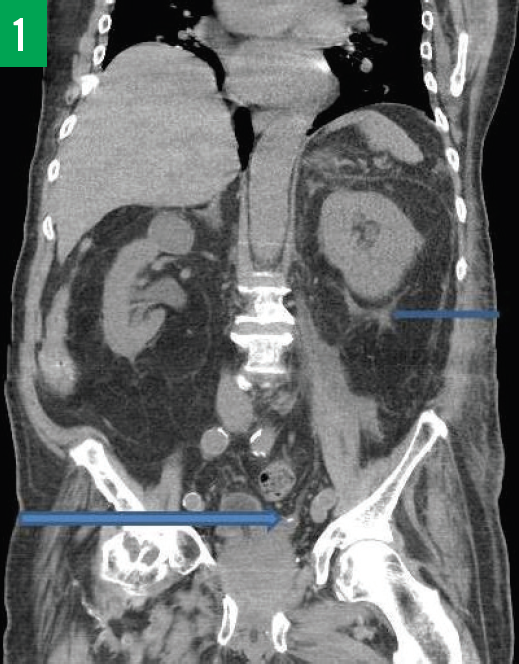

Andrew Rosenthal, MD, MBA; Claire Wunker, MD, MS-IV; Stephen Winfield, MD; Sharon Sukhdeo, MS-IV, MD

A 59-year-old man presented to the emergency department for acute-onset diffuse abdominal pain for the past 2 days, which he described as moderate to severe, sharp, and nonradiating.

12/05/2016